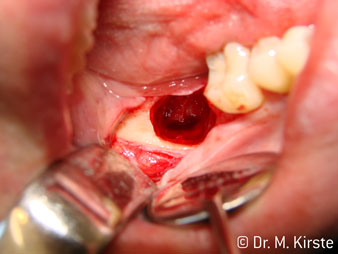

Die Winkelwahl des 45° Handstücks bringt viele Vorteile in der Anwendung. Chirurgisch tätige Kollegen, und für diese ist das Handstück in erster Linie entwickelt worden, werden schnell bemerken, dass man sehr gezielt arbeiten kann. Insbesondere bei der Weisheitszahnentfernung (Abb. 2) bedarf es keiner großen Weichteilabspreizungen im Wangenbereich (Abb. 3). Die Handstückkopfgestaltung kombiniert mit leichten Kopfdrehungen bei der Präparation lassen ein sicheres und schnelles Arbeiten im retromolaren Bereich zu.

Abb. 2